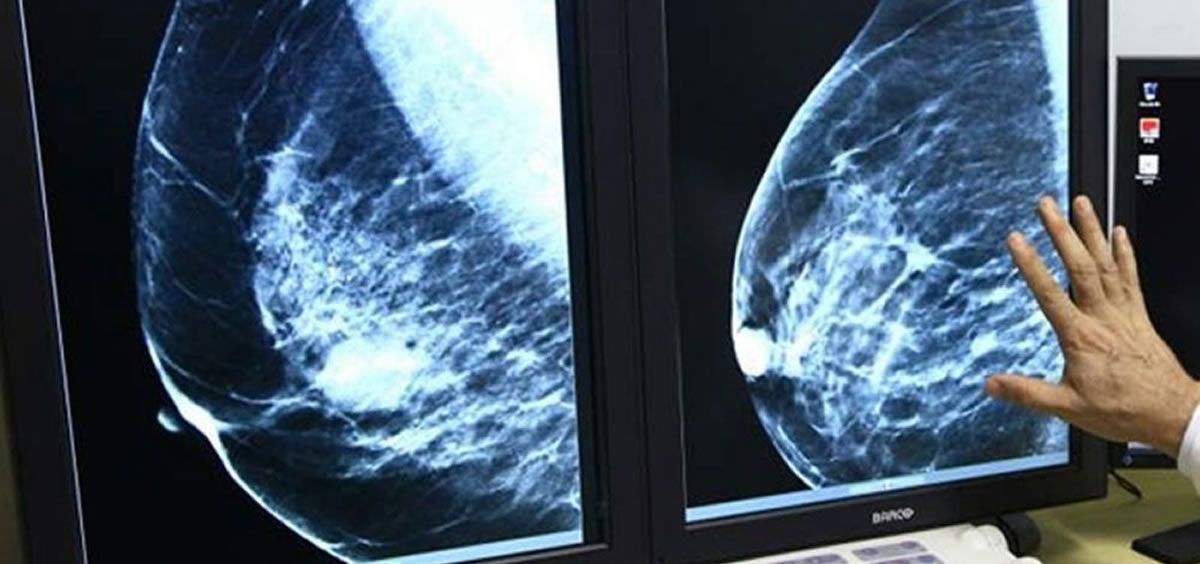

Un equipo de médicos del Instituto Nacional del Cáncer de Esados Unidos ha conseguido, por primera vez, erradicar por completo un cáncer de mama avanzado con metástasis en otros órganos a través de un tratamiento de inmunoterapia. Estos nuevos procesos "adiestran" al sistema inmune del paciente para que tenga la capacidad de reconocer y eliminar las células del cáncer.

La paciente, mujer de 49 años, padecía un cáncer de mama avanzado que no respondía a ninguna terapia convencional, como la quimioterapia o los tratamientos hormonales, por lo que se intentó ir un poco más allá. Los expertos secuenciaron el genoma completo del tumor e identificaron las 62 mutaciones que había acumulado. Cada uno de estos errores en el ADN pueden generar fragmentos de proteínas conocidas como neoantígenos. Los médicos analizaron los linfocitos de la paciente en cultivos celulares, seleccionaron los que eran capaces de identificar cuatro de esas moléculas mutadas y los multiplicaron en el laboratorio.

Finalmente, la paciente recibió una sola inyección que contenía unos 82.000 millones de linfocitos seleccionados, desarrollados en base al perfil genético de su tumor, con el objetivo de que atacaran a los los focos malignos. El resultado fue exitoso: el cáncer en la mama, en el hígado y en otros órganos desaparecieron por completo. A día de hoy, la paciente lleva dos años sin rastro de células cancerígenas.